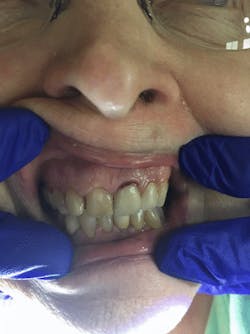

As I applied it to the facial margin of her No. 9 crown, the exposed root turned black, indicating presence of decay (figures 3 and 4). I followed up with the second solution of potassium iodide on No. 9. A creamy white precipitate formed and transformed to a clear precipitate, replacing the black stain (figure 5).

Figure 3: No. 9, prior to the Riva Star application

Figure 4: No. 9, after the application of Riva Star silver diamine fluoride

Figure 5: No. 9, after the application of Riva Star potassium iodide solution